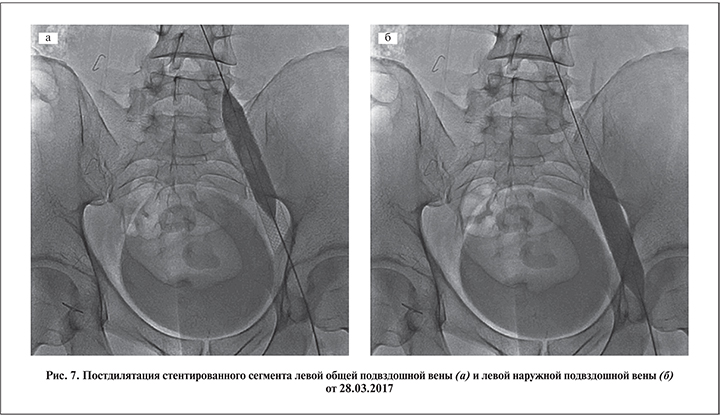

Выраженная тазовая симптоматика на фоне рецидивного варикоцеле, наличие компрессии подвздошных сосудов и коллатерального кровообращения, по данным флебографии, служили признаком илеопельвикальной венозной гипертензии и определили показания к ангиопластике и стентированию левой общей подвздошной вены. 28.03.2017 в ГКБ им. Е. О. Мухина пациенту выполнена операция баллонной ангиопластики и стентирование левой общей подвздошной вены. Оперативное лечение синдрома подвздошной венозной компрессии включило следующие этапы: 1) пункцию левой наружной подвздошной вены; 2) мультипроекционную интраоперационную флебографию; 3) баллонную ангиопластику левой общей подвздошной вены; 4) имплантацию стента в левую общую подвздошную вену; 5) постдилятацию стентированого сегмента; 6) контрольную флебографию.

Поскольку фиброзные внутрипросветные спайки (шварты) в компрессированной подвздошной вене встречаются в большинстве случаев, будучи неизбежным патогенетическим звеном этого заболевания, проведение ангиопластики перед стентированием мы считали обязательным этапом операции (рис. 5).

Для имплантации использовали венозный стент Wallsten-Uni Endoprothesis («Boston Scientific») из сплава Elgiloy (сплав на основе никеля, кобальта и хрома) диаметром 16 мм, длиной 90 мм (рис. 6).

Постдилятация стентированного сегмента также служила обязательным этапом оперативного лечения подвздошной венозной компрессии (рис. 7 а, б).